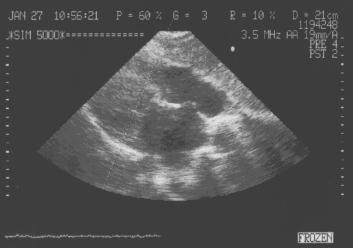

1. Аневризматическое выпячивание в сторону правого предсердия в области овального окна, усиливающееся в систолу (рис.159 - 160).

Аневризматическое выпячивание межпредсердной перегородки

в сторону правого предсердия в области овального окна.

Рис.159

Аневризматическое

выпячивание

межпредсердной

перегородки в

сторону правого

предсердия в области

овального окна.